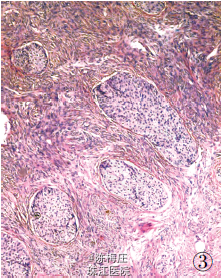

最后诊断:右乳神经内分泌癌;结肠腺癌;左侧卵巢Brenner 瘤。

遂行右乳肿物切除术+ 乙状结肠癌切除术及左侧附件切除术。术中所见:右乳肿物分叶状,与周围界清;乙状结肠肿物与周围无粘连;左侧卵巢肿物包膜完整,未见腹水。术后病理显示右乳腺内分泌癌,乙状结肠腺癌,左侧卵巢Brenner 瘤。